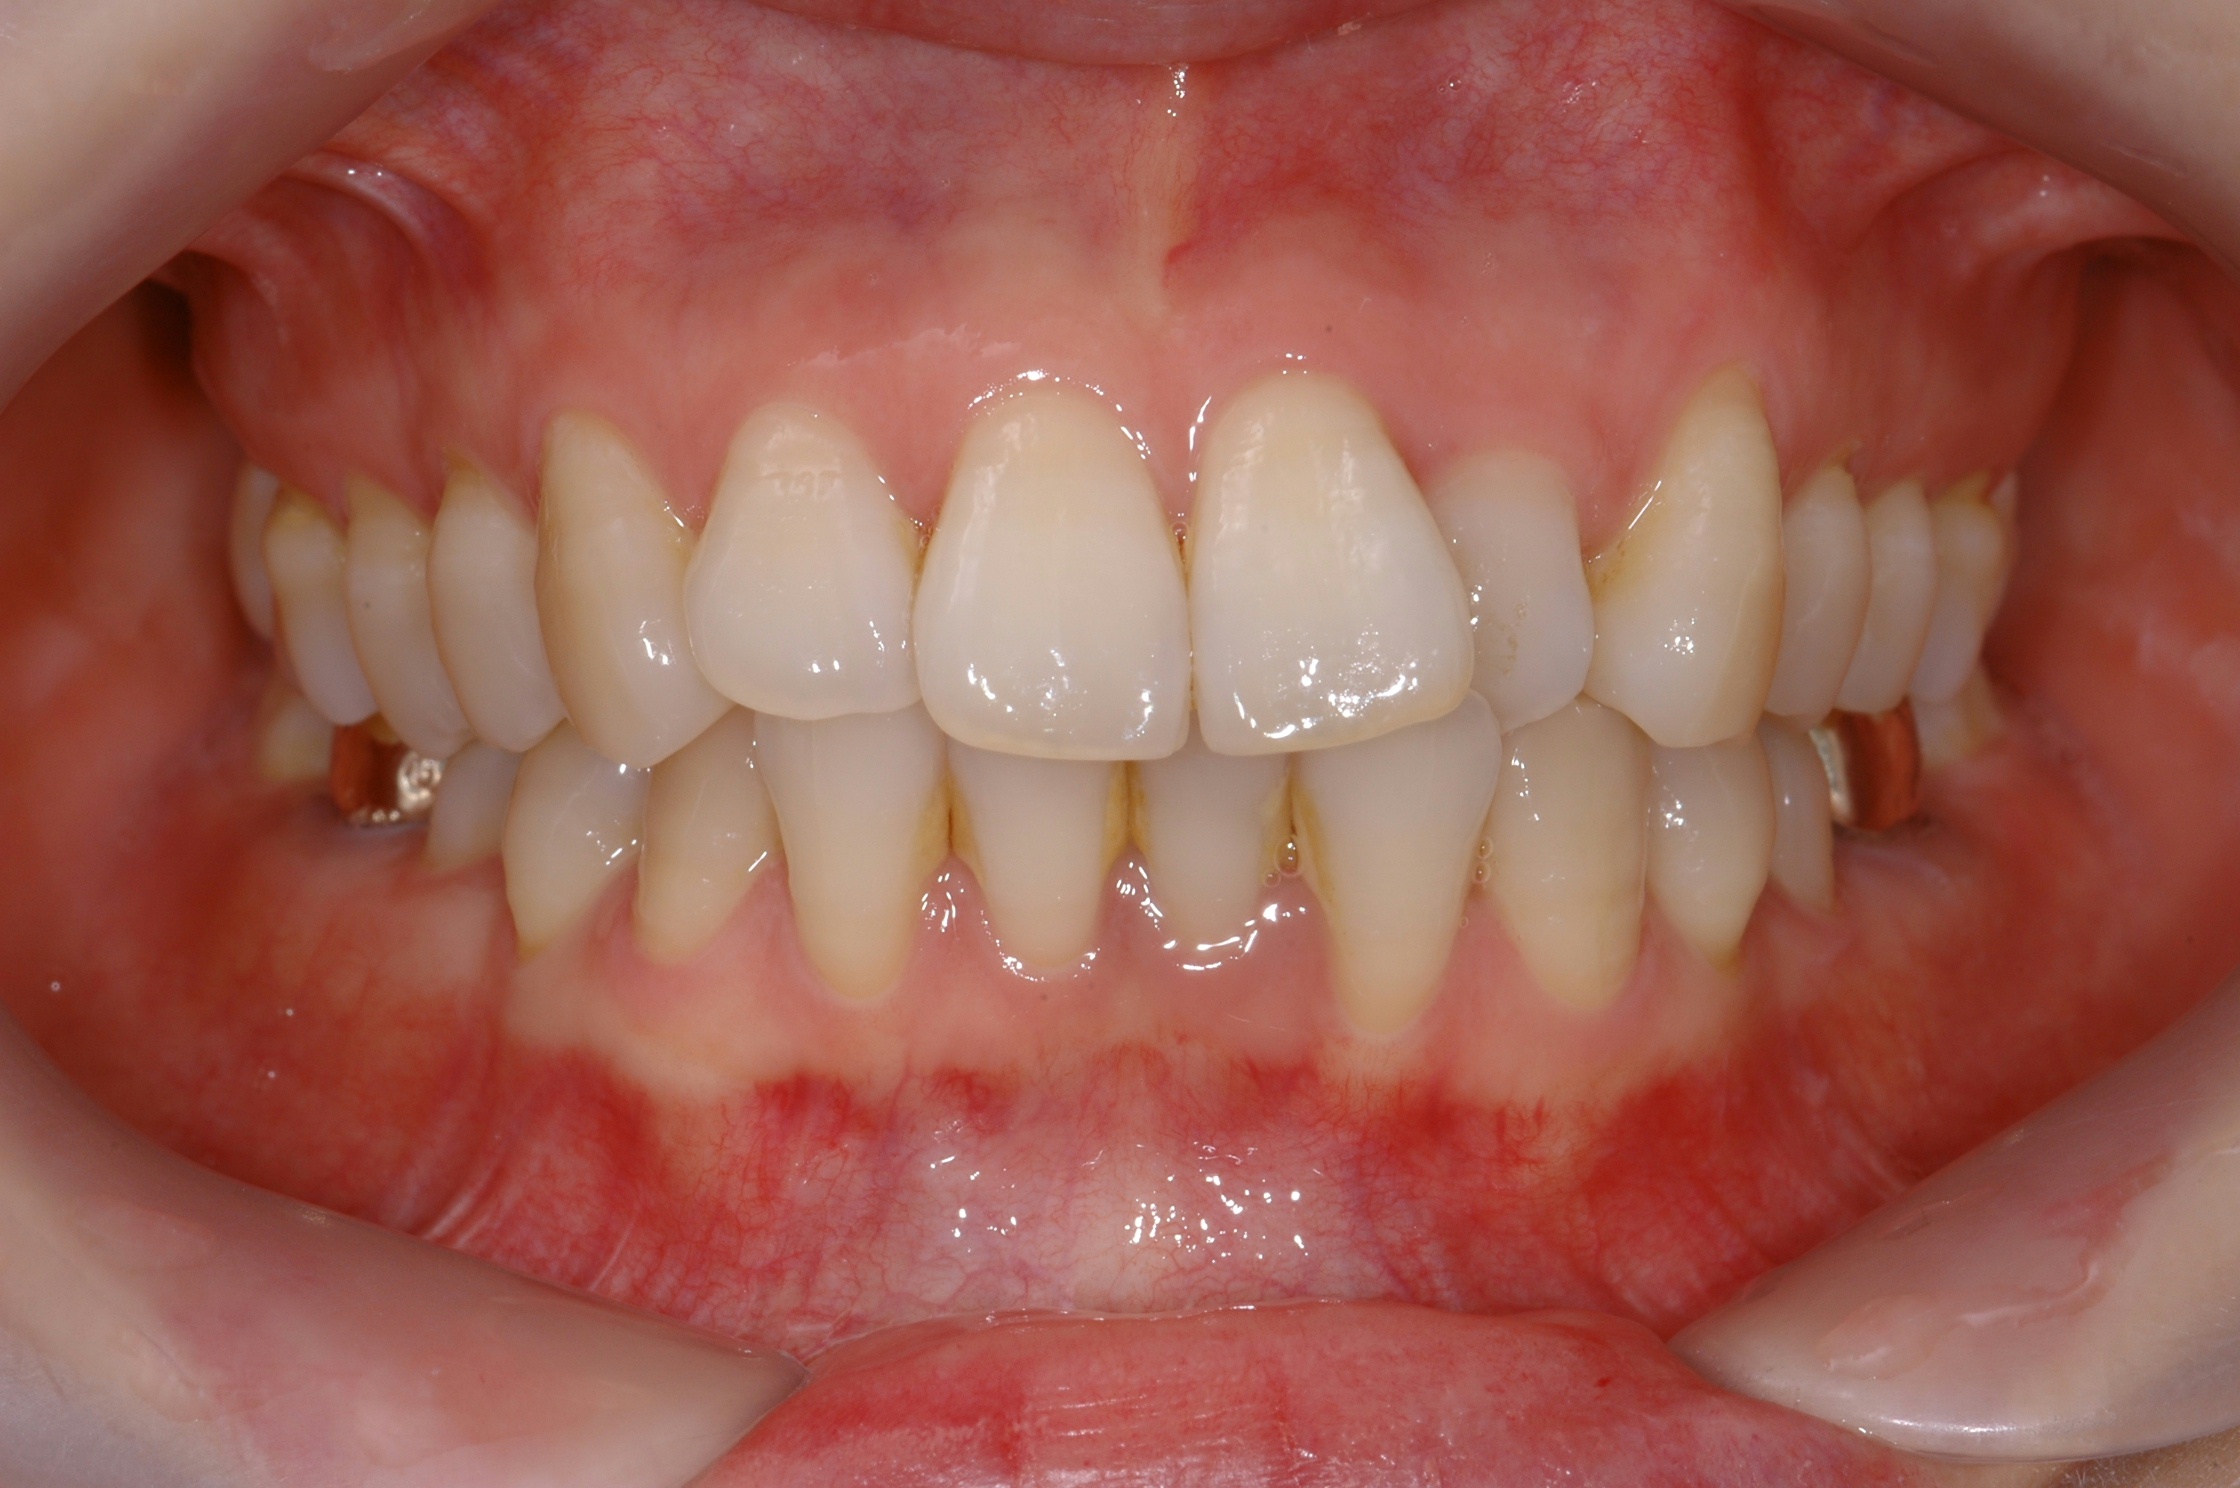

치료 후 사진입니다.